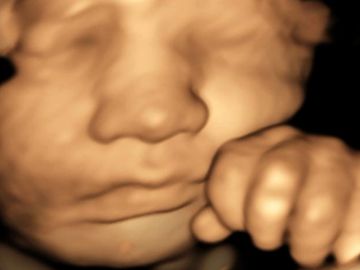

Memories that last a lifetime.